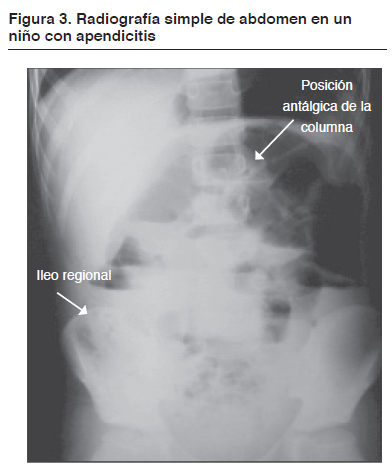

- Estudios por imagenes